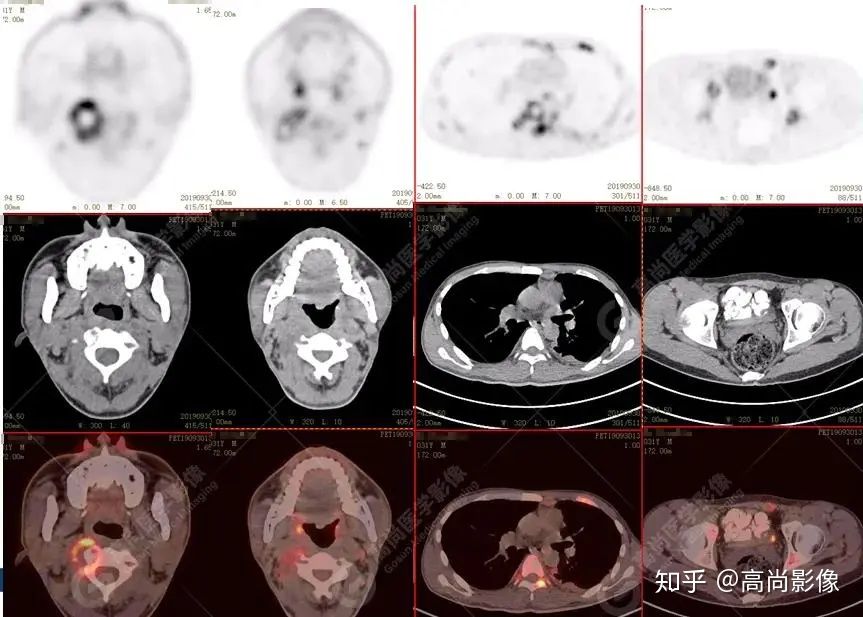

全身多發(fā)高代謝腫大淋巴結(jié),中央代謝缺損

【PET/CT提示】雙肺、左側(cè)胸膜多發(fā)結(jié)節(jié)影,全身多處骨質(zhì)破壞,全身多發(fā)淋巴結(jié)腫大,代謝攝取不均勻性增高。

2.全身多系統(tǒng)、多形態(tài)、多發(fā)病灶(肺部、胸膜、淋巴結(jié)、骨),18F-FDG攝取不均性增高;

特征:肺部病灶簇狀分布,上葉尖段及下葉背段為著;腫大淋巴結(jié)分布不對稱,無融合、中央有壞死改變,與淋巴瘤、轉(zhuǎn)移瘤等有一定的鑒別診斷意義;

診斷意見:綜合考慮感染性病變(結(jié)核),建議相關(guān)實(shí)驗(yàn)室檢查。